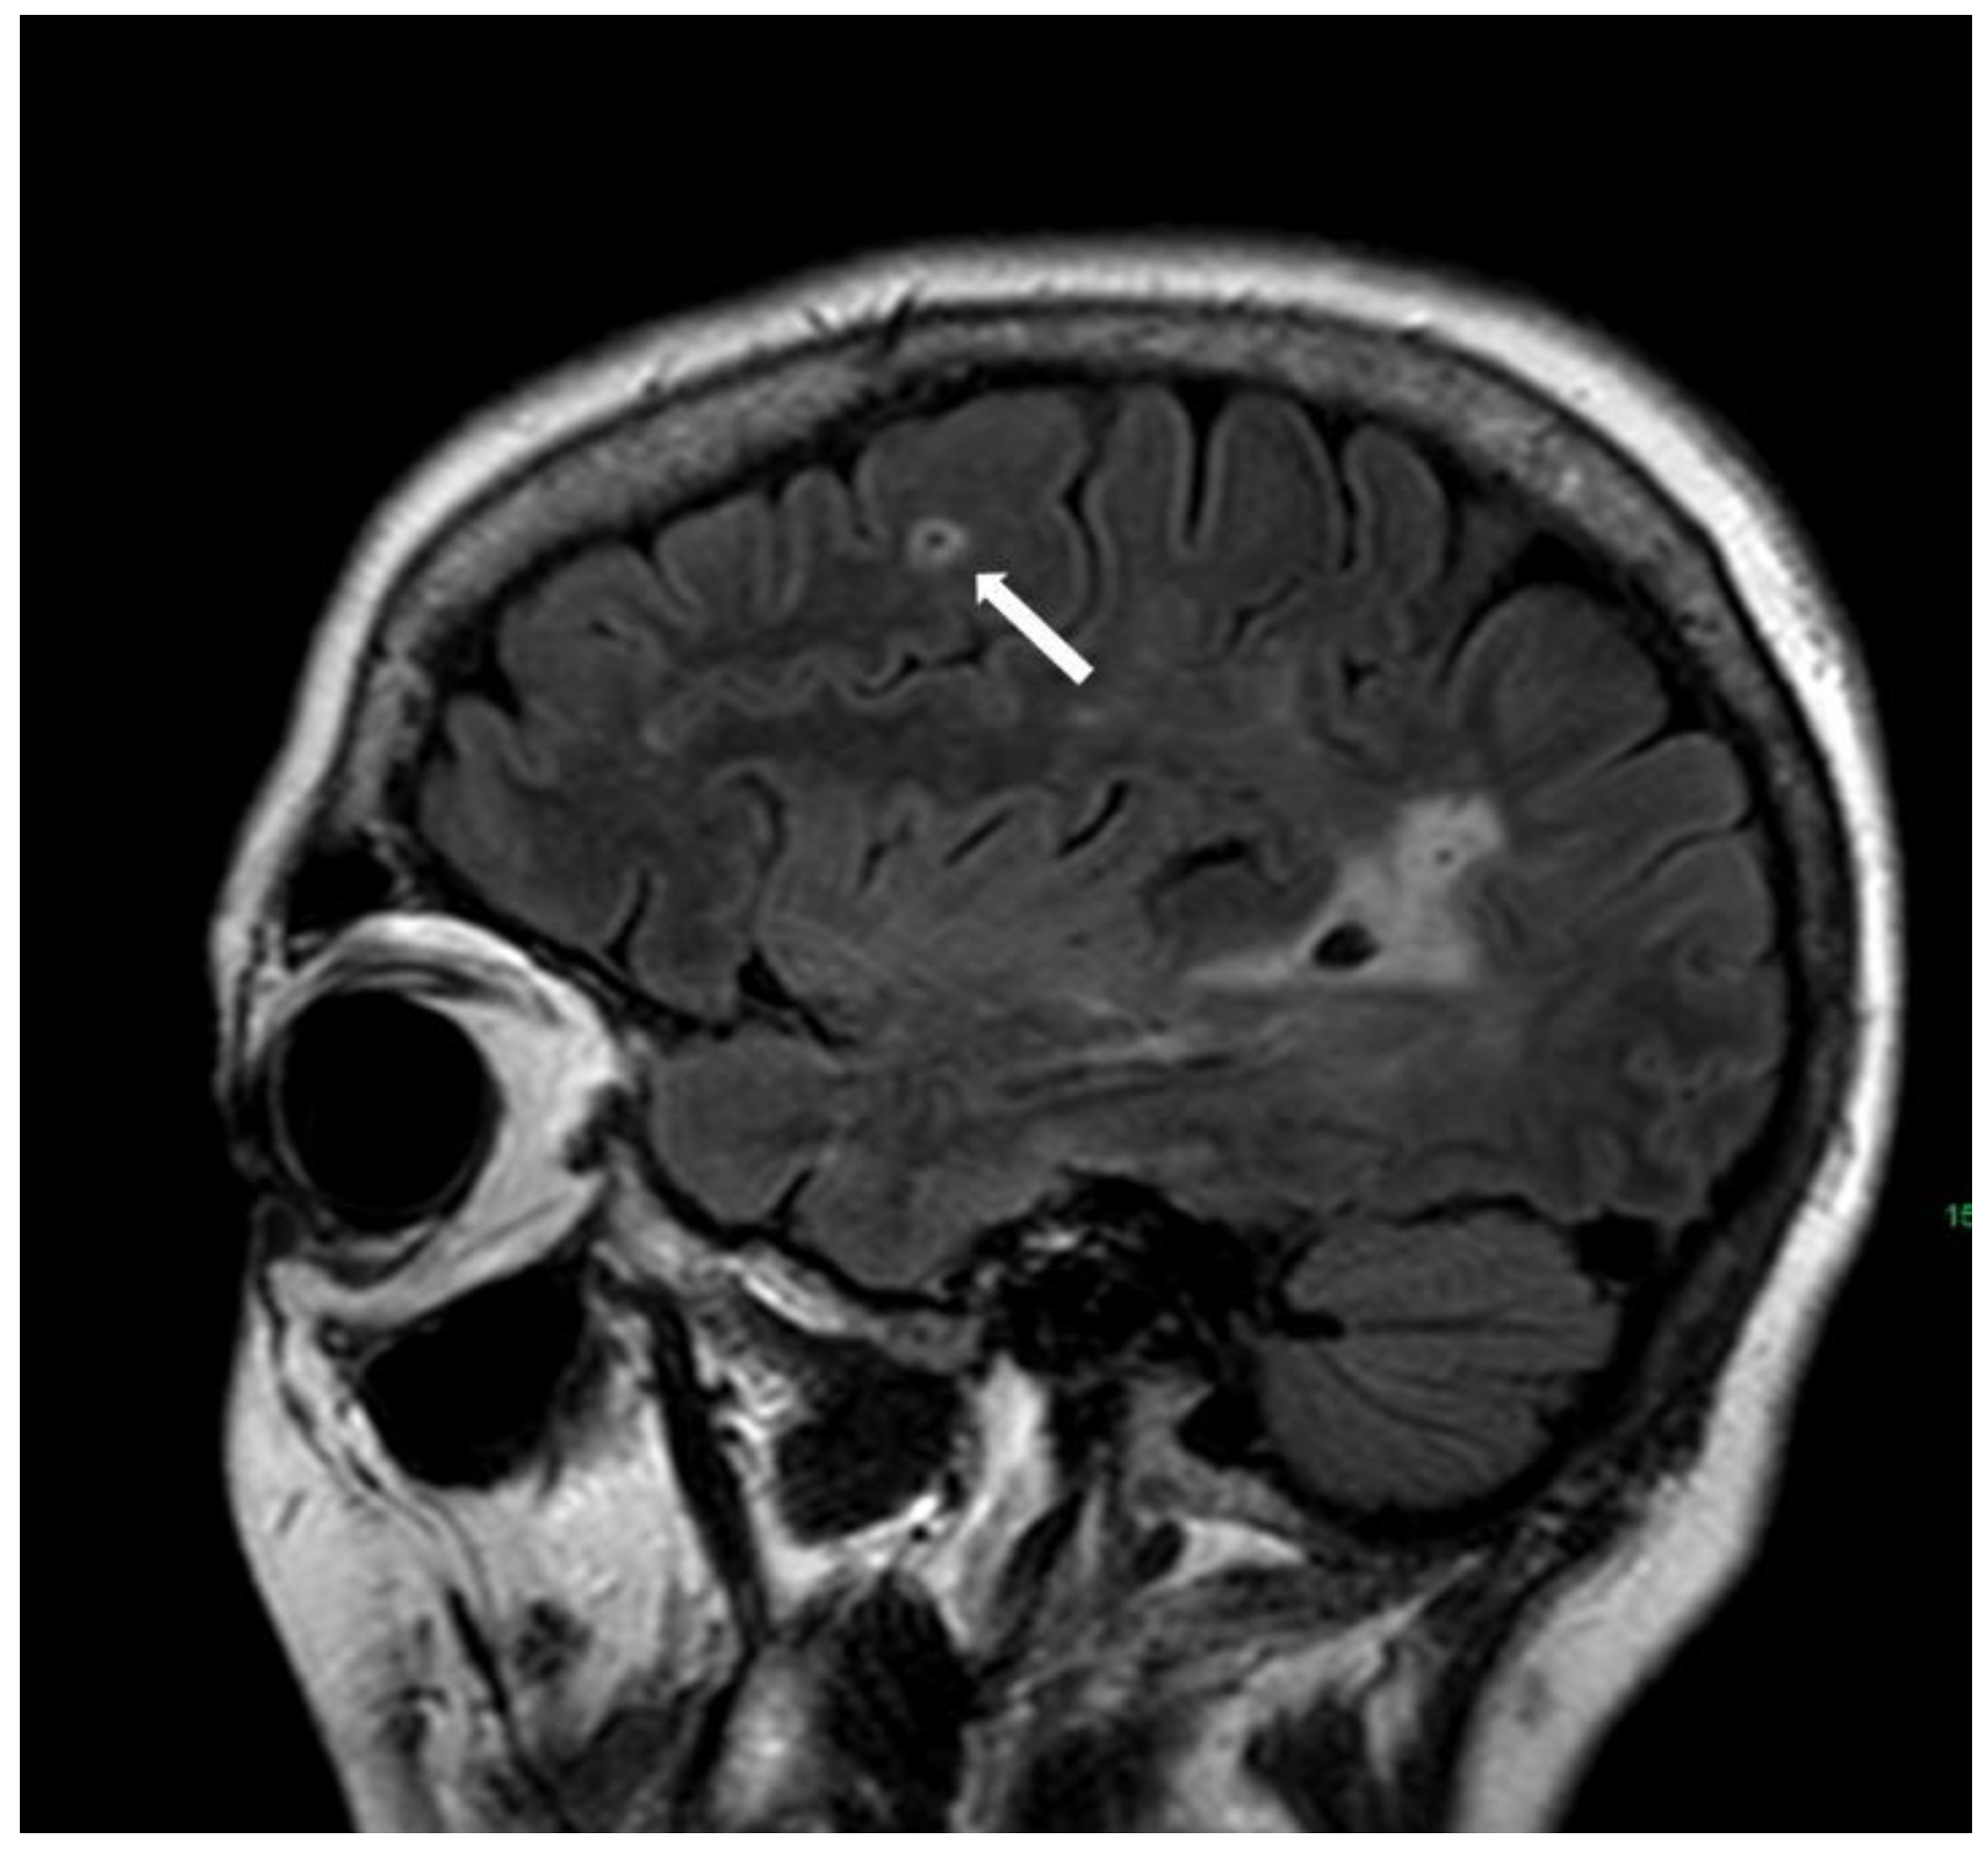

5.1.4. Cortical Superficial Siderosis

- Charidimou, A.; Linn, J.; Vernooij, M.W.; Opherk, C.; Akoudad, S.; Baron, J.-C.; Greenberg, S.M.; Jäger, H.R.; Werring, D.J. Cortical superficial siderosis: Detection and clinical significance in cerebral amyloid angiopathy and related conditions. Brain 2015, 138, 2126–2139. [Google Scholar] [CrossRef]

- Charidimou, A.; Boulouis, G.; Roongpiboonsopit, D.; Xiong, L.; Pasi, M.; Schwab, K.M.; Rosand, J.; Gurol, M.E.; Greenberg, S.M.; Viswanathan, A. Cortical superficial siderosis and recurrent intracerebral hemorrhage risk in cerebral amyloid angiopathy: Large prospective cohort and preliminary meta-analysis. Int. J. Stroke 2019, 14, 723–733. [Google Scholar] [CrossRef] [PubMed]